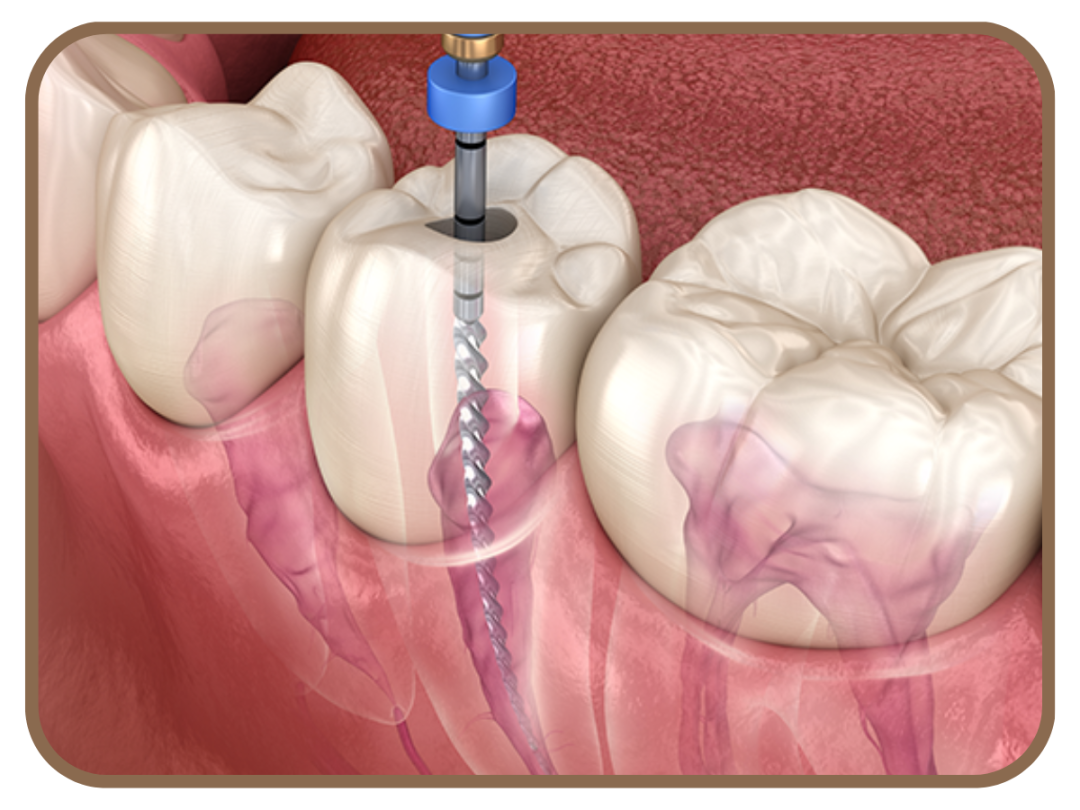

💎 Especialista em tratamento de canal (endodontia)

Eliminação da dor e infecção com tratamentos de canais modernos, seguros e eficazes, preservando a estrutura dentária e evitando extrações desnecessárias.

Clique Aqui e Tire suas Dúvidas